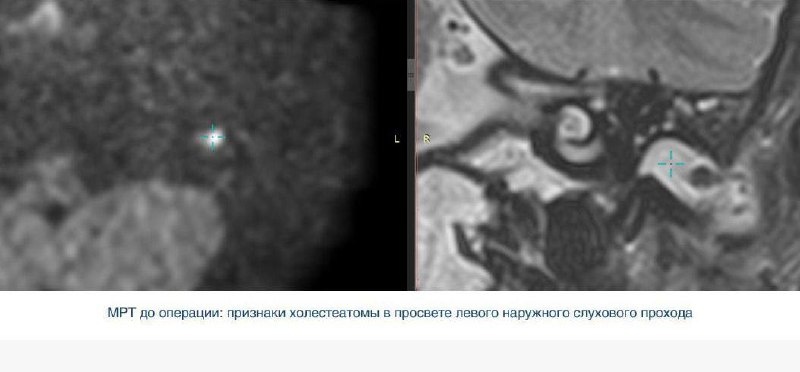

— холестеатому — доброкачественное образование, разрушающее структуры уха;

У мальчика с 10 лет отмечалось ухудшение слуха и периодические выделения из уха, однако лечение долгое время не проводилось. При обследовании врачи выявили:

— сужение слухового прохода;

— аномалию развития слуховых косточек и ушной раковины.

После подготовки и купирования воспаления пациент был направлен на плановую операцию.